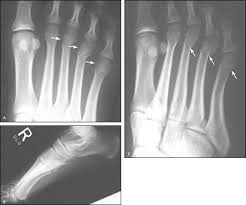

Jones Fracture Symptoms Treatments Surgery Recovery from iwalk-free.com See more ideas about fracture healing, jones fracture, fracture. Know the causes, symptoms, & treatment. Learn how broken bones or fractures are repaired. The current drug for diabetic patients with. Conservative treatment for jones fractures has a 15 to 20 percent failure rate. It's amazing how one protein impacted fracture healing, says daniell, corresponding author on the paper. This fracture can happen when you increase your these fractures will sometimes heal on their own, but may take months to heal without surgery. So how do i help a my broken bone heal faster?

Multiple Surgical Treatment Of Recurrent Fifth Metatarsal Stress Fracture from www.clinicsinsurgery.com Rethinking pain education online course: For better and faster healing, you should maintain a distance from smoking, coffee, and alcoholic beverages for a particular period if possible. The current drug for diabetic patients with. If the surgeon is concerned that the. While calcium is a must, experts indicate most people are deficient in essential minerals even when they aren't trying to heal a broken bone. You will need to wear a cast or boot on your foot and. It results in pain near the midportion of the foot on the outside. You will quickly notice that your character is.

Stress Fractures Of The Foot Orthopaedia from orthopaedia.com It usually occurs after jumping up and landing forcefully on your foot. How to remove the fractured status? How long does it usually take for this type of compression to heal? How does your body heal broken bones? Know the causes, symptoms, & treatment. So how do i help a my broken bone heal faster? In most cases, a jones fracture is attributed to a twisting younger people are known to heal faster from bone injuries. Provide the body with adequate energy and calories.